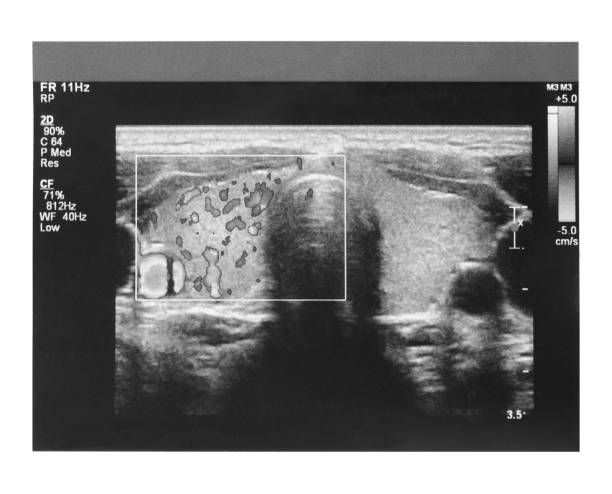

·       Mama (estudio complementario a mamografía)

·       Tiroides y cuello